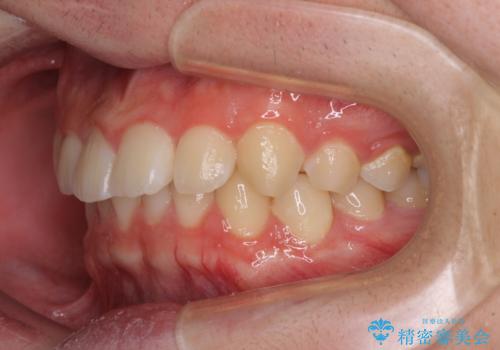

- 前方に傾斜した前歯を気にして来院された患者様です。

強く食いしばってしまう癖があり、下顎前歯に押し出されて上顎前歯が前方へ斜めに突き出している状態でした。

IPR(歯と歯の間を削る)を多用して、インビザラインにて矯正治療を行うこととしました。

口元を引っ込めるためのゴムかけを頑張っていただき、満足のいく上顎前歯の傾斜へ改善することができました。